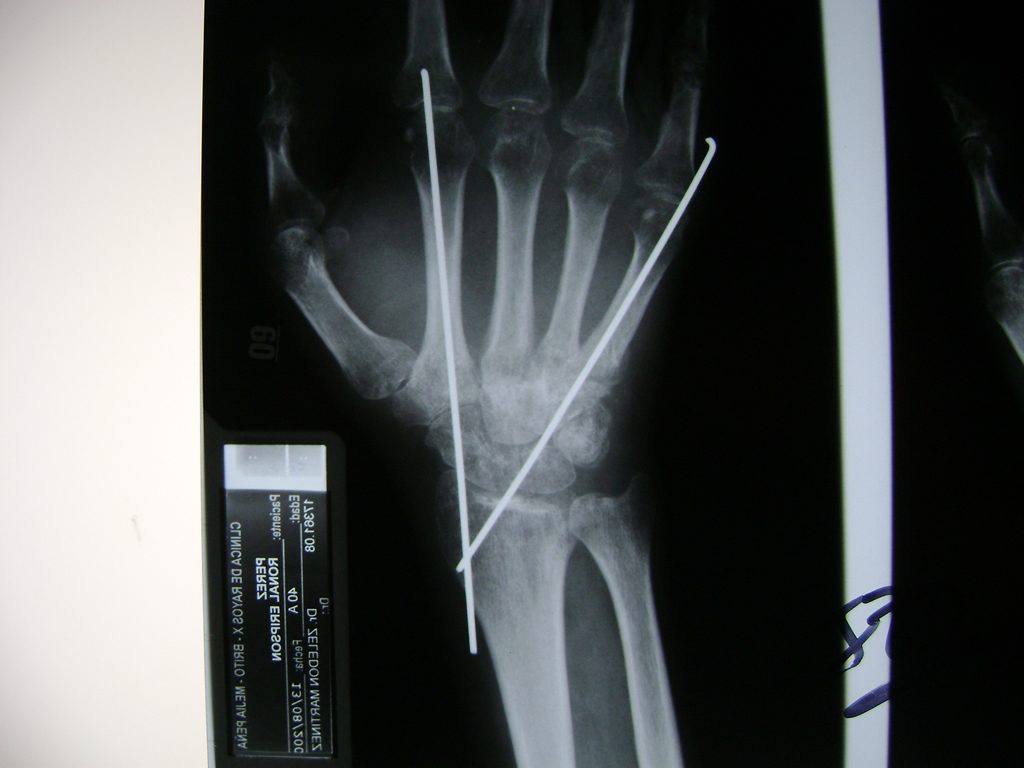

Cirugías de Muñecas

Los procedimientos más comunes en cirugía de la mano son aquellos destinados a reparar traumatismos, incluyendo lesiones de tendones, nervios, vasos sanguíneos, y articulaciones; huesos fracturados; y quemaduras, cortes, y otros daños de la piel.